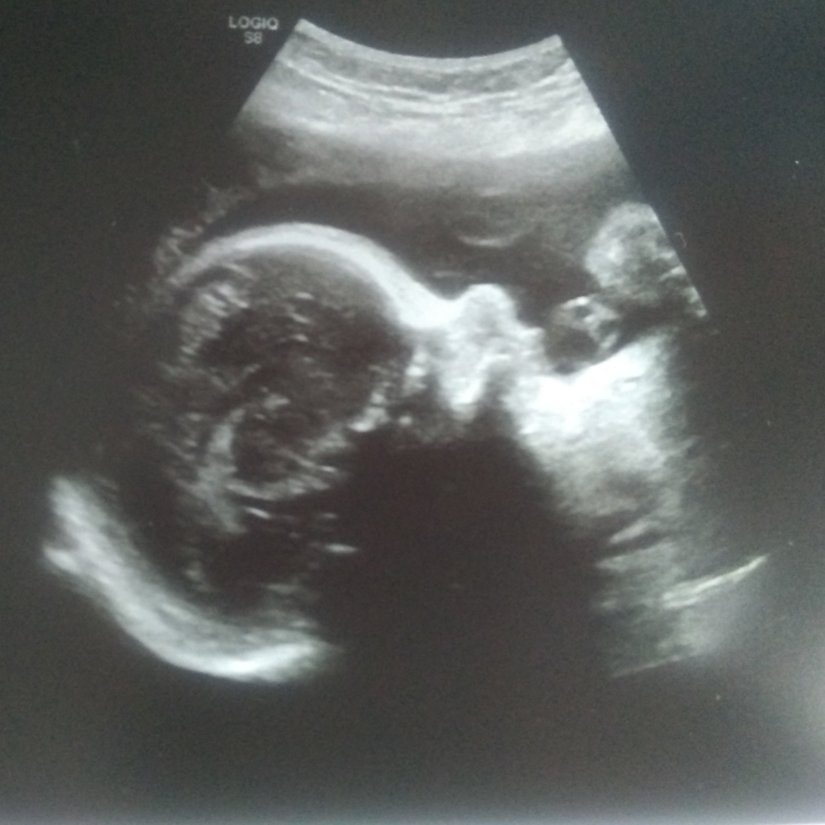

We had a third ultrasound this week. At our 20 week ultrasound a calcium buildup was detected on baby’s liver so we went in to follow up on that. Unfortunately it is still present but everything else is looking great. Also he is head down! So movement wise he keeps going head down and spinning in a circle. He also will move head position from completely down but not engaged to almost sideways.

Ultrasound 29 weeks